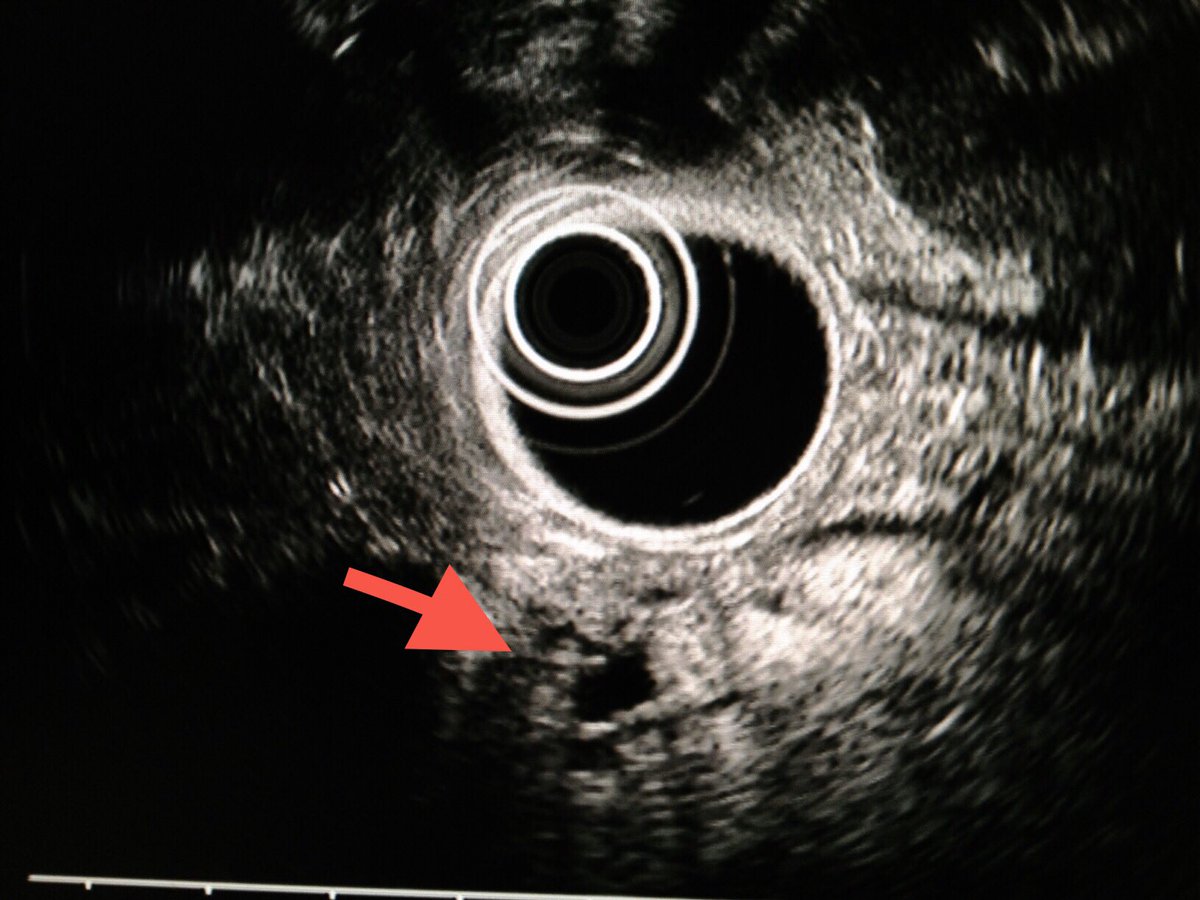

Ampullary cancer

منظار الأشعة الصوتية يظهر انسداد القناة المرارية الرئيسية بورم في فتحة اوددي. أعراض المرض صفار والتهاب في القنوات المرارية في بعض الأحيان. قد يشخص خطئا بحصوة في القناة المرارية إذا لم يتم عمل أشعة النظار الصوتية